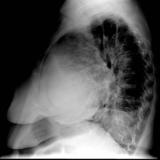

Case 1 Lat